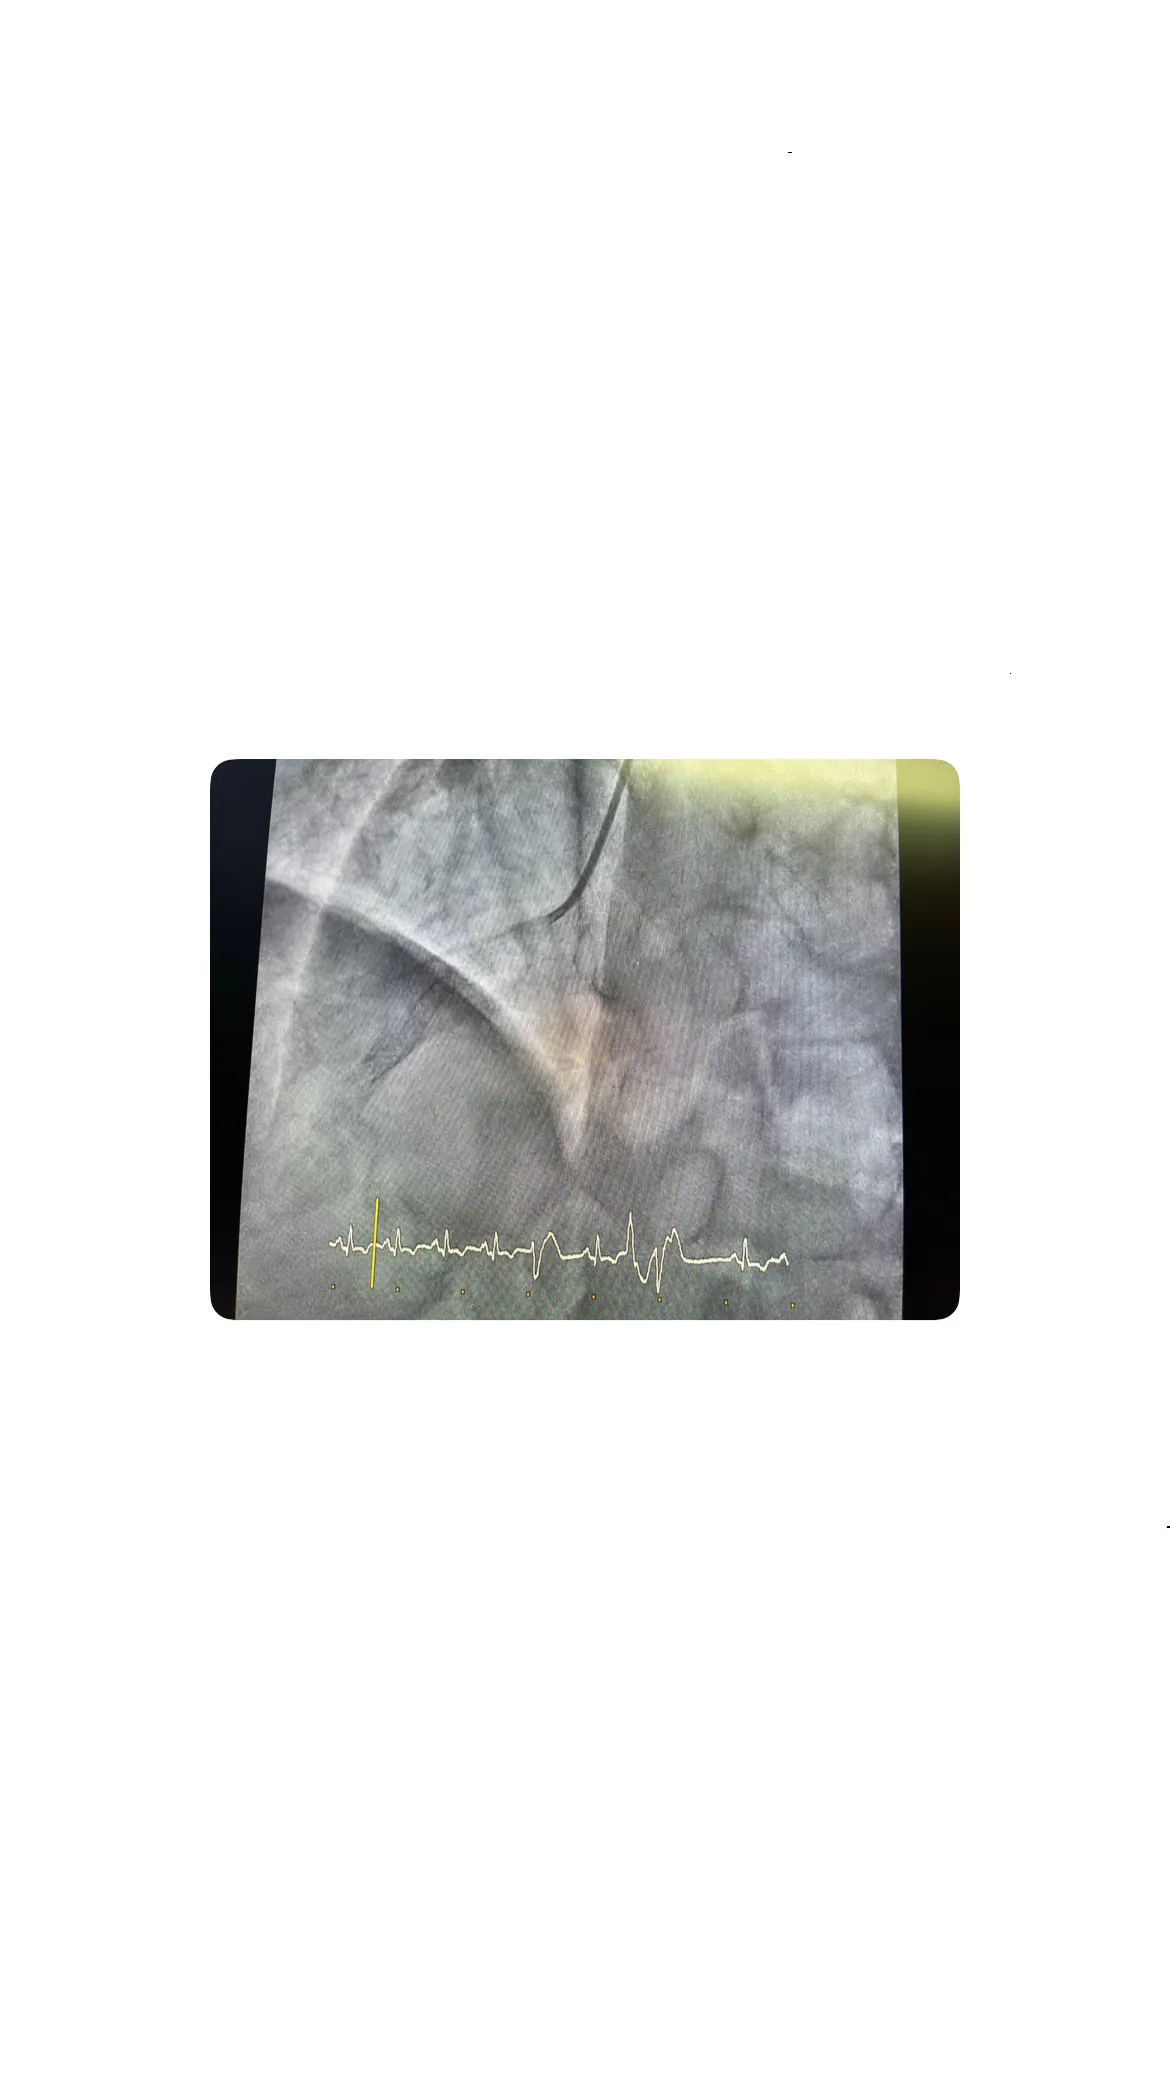

Tratamiento de la lesión: predilatación y balón farmacoactivo

Predilatación con varios balones

La predilatación con varios balones fue un paso crucial en el tratamiento de la reestenosis. Este procedimiento ayuda a preparar la arteria para la implantación del balón farmacoactivo, asegurando que el tratamiento sea más efectivo y que el flujo sanguíneo se restablezca adecuadamente.